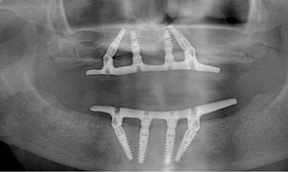

Fig 3. At 4 years and 5 months follow-up, reparative bone had formed to the apices of all implants.

Figure 3

Fig 4. Four zygoma implants placed using “quad” approach.

Figure 4

Fig 5. Final restoration remains in function.

Figure 5

The Toronto Conference in 1982, chaired by Professor George Zarb and presented by Professor Per-Ingvar Brånemark, was a seminal event that changed edentulous treatment planning concepts irrevocably. No longer was it necessary to rebuild lost bone through grafting alone in either arch. The severely atrophic mandible, for example, could be treated with as few as four implants used to support a bone-sparing prosthesis through integrated tooth analogs, as demonstrated in Figure 1 through Figure 3. Here, an 81-year-old patient presented with severe mandibular atrophy (Figure 1) from denture wear since a very young age and had a history of being unable to manage a mandibular prosthesis despite numerous attempts at new denture construction. Four vertical machined-surface osseointegrated implants were placed in 1983 by Professor Brånemark, and all four penetrated the inferior cortex up to 3 mm to 4 mm in depth, as shown on the immediate postoperative panoramic film (Figure 2). At 4 years and 5 months, reparative bone had formed to the apices of all implants (Figure 3), and all of them remained in uncompromised function until the patient passed away at age 90.

Severe maxillary atrophy may have a different etiology compared to that of the mandible, but the resultant resorption is no less debilitating. Grafting in the upper arch is increasingly less common with the advent of implant types such as zygoma that are anchored in remote bone and offer a far less traumatic and functionally improved option, especially for an aging patient. This is illustrated in Figure 4 and Figure 5. The patient had worn both a removable partial denture and full lower denture for more than 40 years with resulting severe maxillary atrophy opposing a natural dentition. Four zygoma implants were placed using the "quad" approach9,10 in lieu of a bone graft procedure (Figure 4). The final restoration remains in function in the patient's seventh decade (Figure 5).